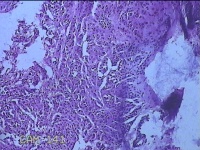

右腋下肿物

性别

女

年龄

28岁

临床诊断

纤维瘤病;皮肤感染

一般病史

无

标本名称

大体所见

灰白粉红色肿物0.3x0.2x0.1cm一个,表面光滑。

制片不太好,看看有没有核分裂,感觉是个皮内痣,问题不大